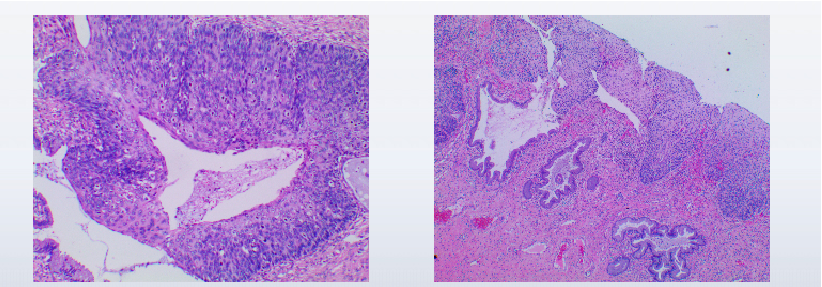

2024-04-11我院宫颈活检病理:宫颈3点活检:高分化鳞状细胞癌;宫颈6点、9点、12点局部呈(CIN I级)伴病毒感染;宫颈管搔刮物,游离的鳞状上皮呈原位鳞状细胞癌图像。

广泛CIN Ⅲ级并累及腺体

各切缘均(-)

盆腔淋巴结(-)

免疫组化:腺上皮P16(-),Ki-67(低表达)